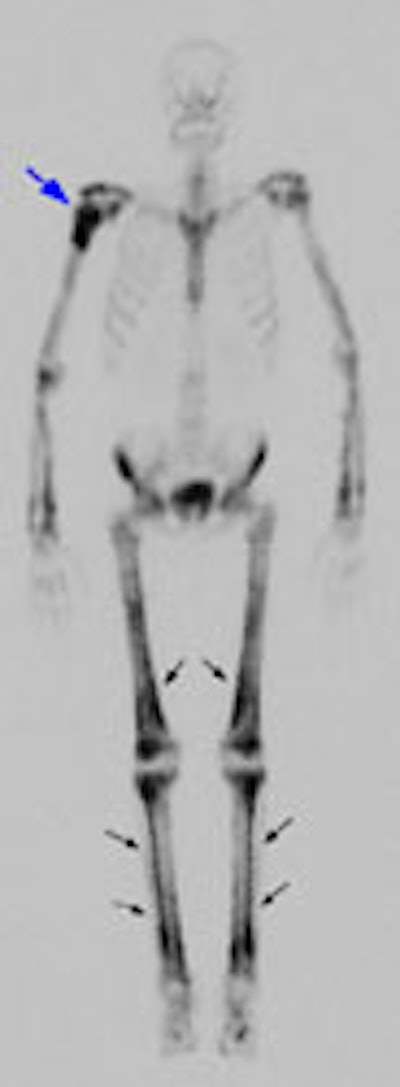

Example 2: This is an interesting case of a patient with non-small-cell lung cancer who complained of right shoulder pain. The bone scan demonstrates a bone lesion in the proximal right humerus (blue arrow) consistent with a metastasis. The scan also revealed linear uptake of tracer along the distal femurs and tibias bilaterally (black arrows). Uptake in the forearms was more irregular. A coned down plain film of the distal left femur demonstrated a solid periosteal reaction (white arrows). The findings are consistent with hypertrophic osteoarthropathy- a paraneoplastic condition seen in association with bronchogenic carcinoma.

NOTE:  Click directly on the image to enlarge.